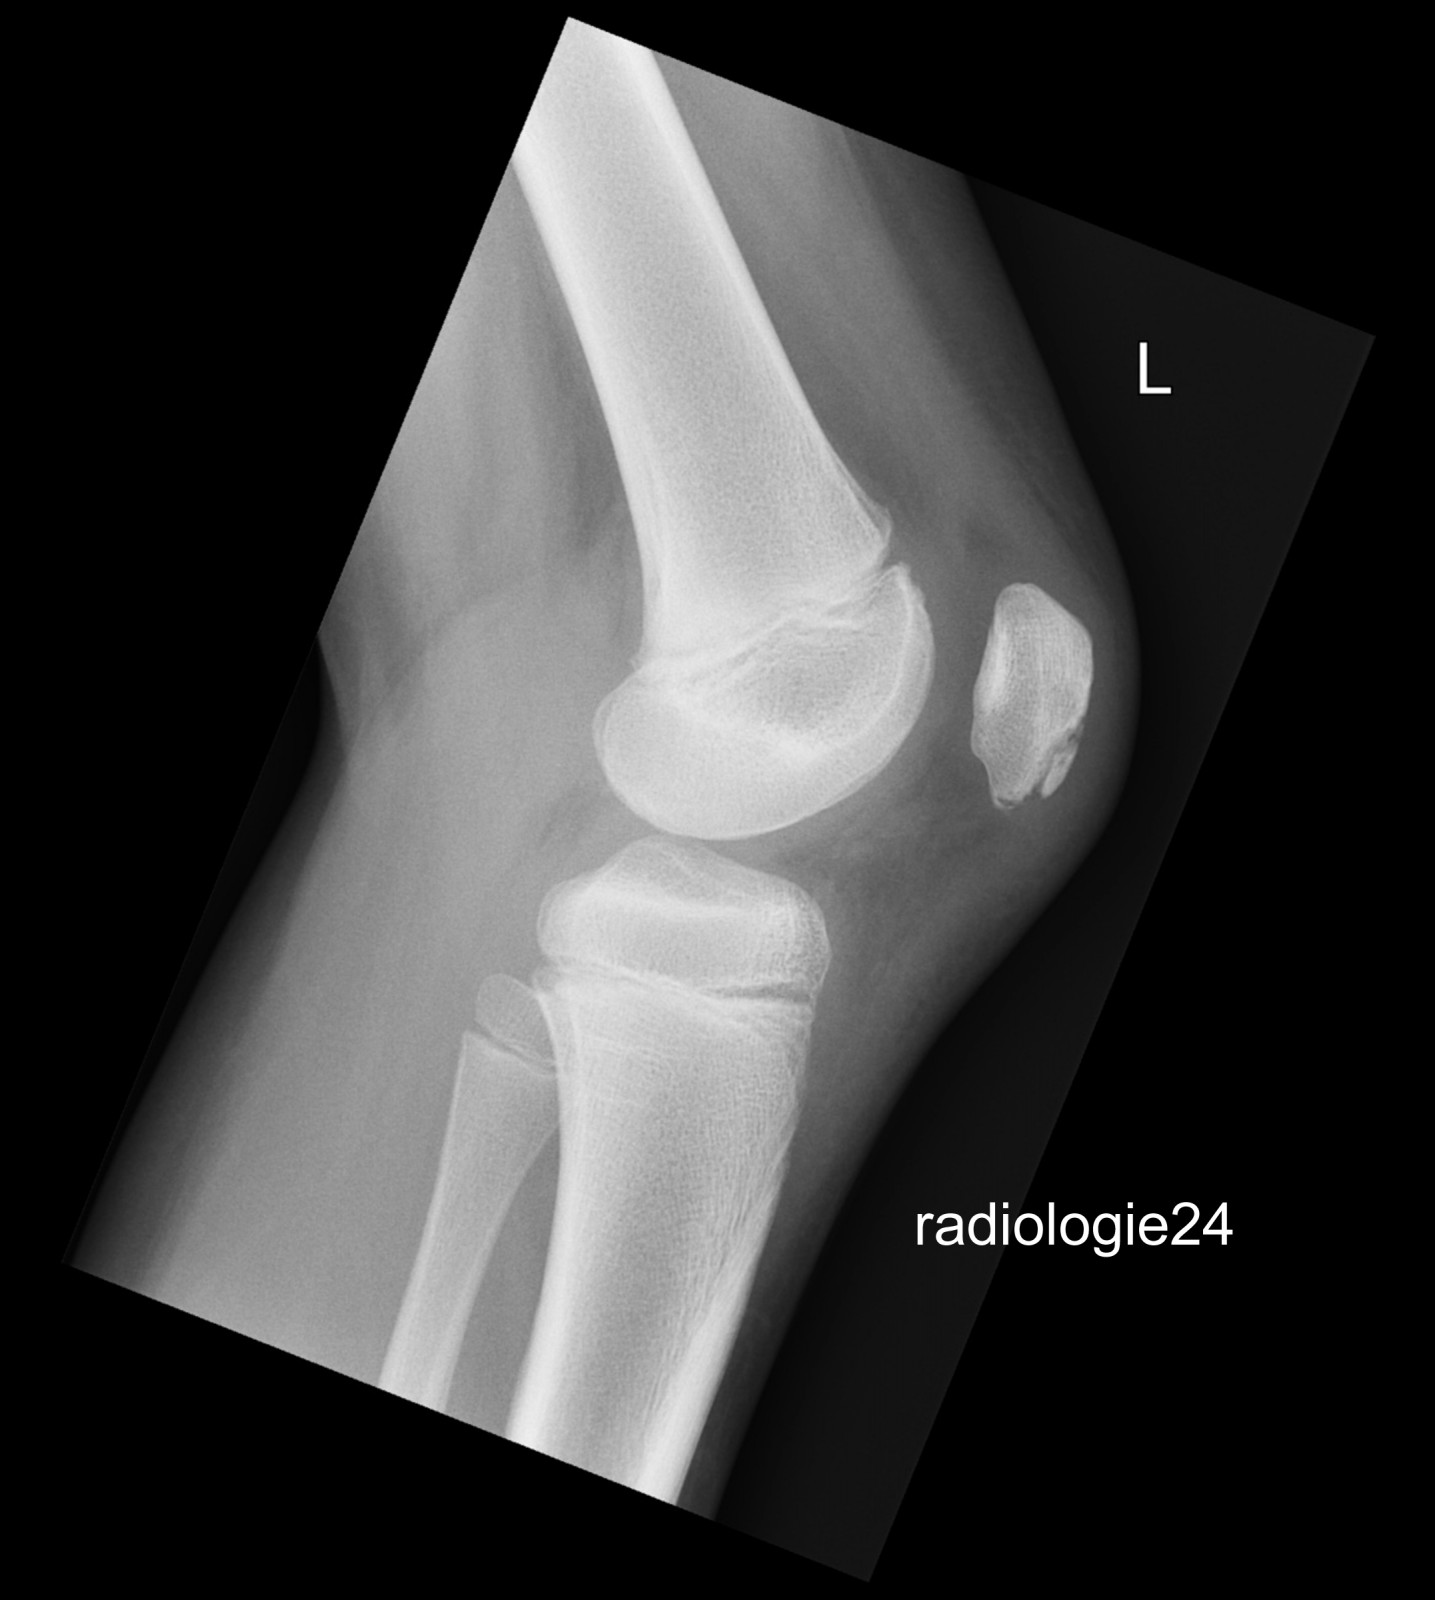

Röntgenfall des Monats März 2018 mit Auflösung

10 jähriger Patient Z.n.Sturz. Schmerzen im Bereich des Kniegelenks Ihre Diagnose?

Link zur Auflösung mit ausführlichem Befund

https://www.radiologie24.ch/radiologie-mediathek/roentgenfall_des_monats